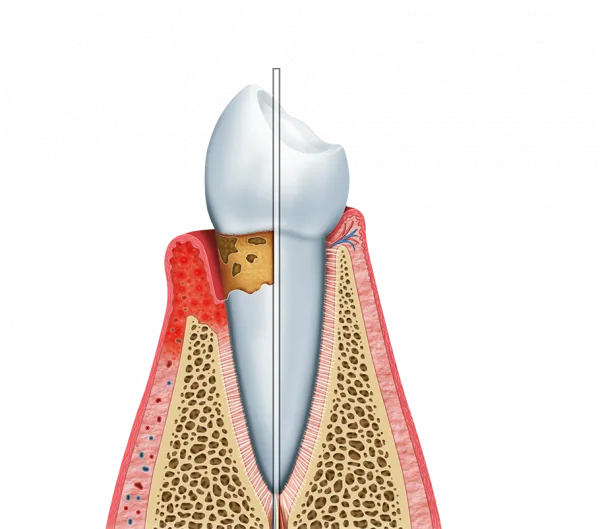

Tratamento de gengivite

O laser é eficaz no tratamento da gengivite, ajudando a remover a placa bacteriana.

Isso reduz a inflamação e promove a saúde gengival.

Tratamento de periodontite

Para casos mais avançados, como a periodontite, o tratamento a laser é uma solução eficaz.

Ele ajuda a eliminar infecções e a preservar os dentes.